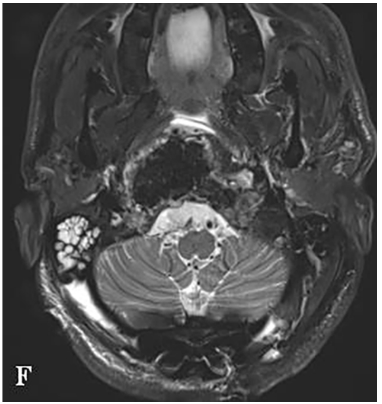

一名26岁男性患者,临床表现为颈部疼痛、严重吞咽障碍及双侧舌下神经麻痹(右侧完全性麻痹伴发舌肌萎缩,左侧为部分麻痹)。MRI与CT影像学检查结果显示,其颅颈交界区存在一直径达10厘米、体积约96.5立方厘米的巨大脊索瘤。该肿瘤呈浸润性生长,广泛侵犯右侧结构,累及范围包括椎前间隙、下斜坡、双侧枕骨髁、第一颈椎(C1)前弓以及第二颈椎(C2)齿状突。巨大肿瘤已导致脑干受压及双侧椎动脉移位,并向硬膜内扩张。

术前MRI与CT影像分别揭示了肿瘤的巨大范围及其对斜坡-枕骨髁造成的溶骨性破坏。主刀团队评估认为,肿瘤已对颅颈交界区骨质结构造成广泛侵蚀,术后极有可能出现颅颈不稳定。因此,手术方案确定为经远外侧经髁入路,施行显微镜与神经内镜双镜联合肿瘤切除术,继而进行枕颈融合术(OCF)。